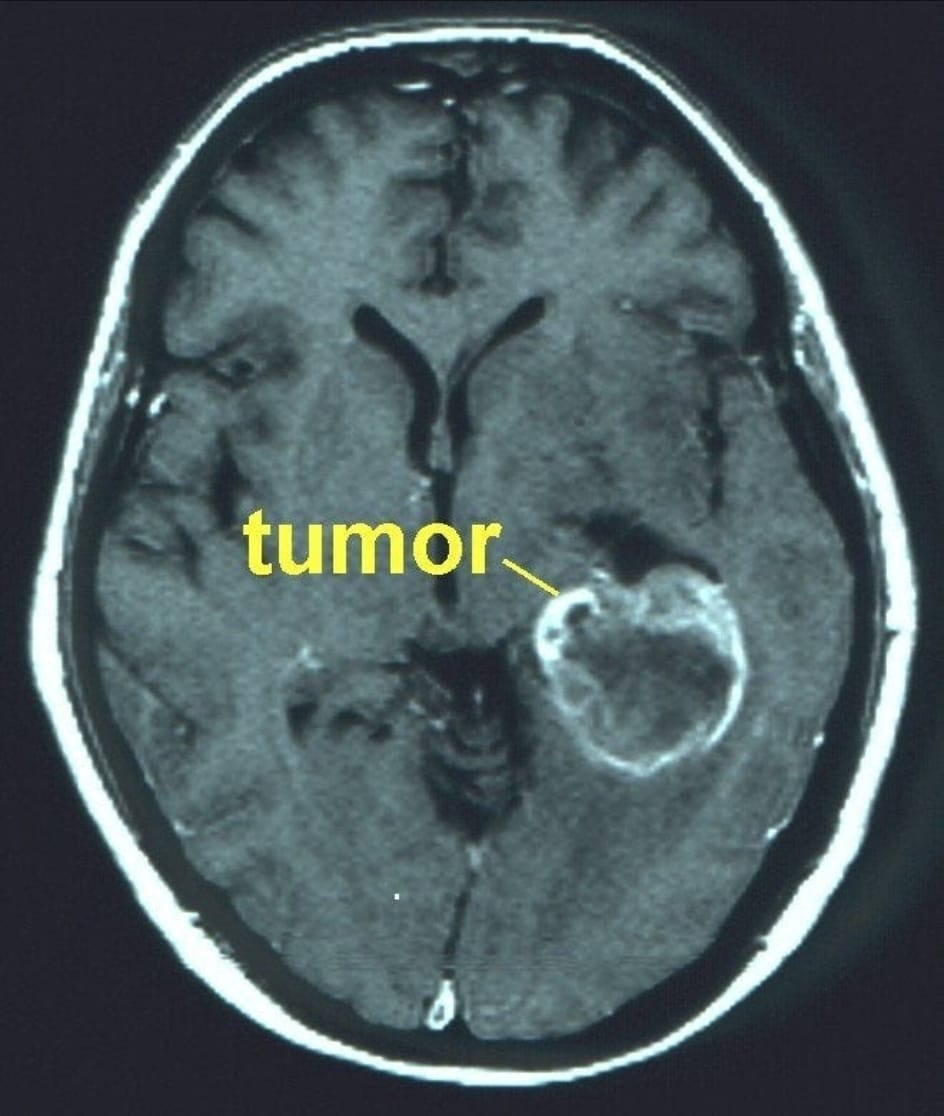

Um estudo pré-clínico inovador publicado na ACS Biomaterials Science & Engineering revelou que a ivermectina nanoformulada administrada por via intranasal reduziu o tamanho do tumor de glioblastoma em 70% — em uma dose menor do que a dose antiparasitária humana aprovada — tudo isso sem nenhum traço de toxicidade no cérebro, sangue ou pulmões.

Tamanho do tumor reduzido em 70%.

Após apenas 10 dias de tratamento:

· O tamanho médio dos tumores de controle foi de 254 mm³

· Os tumores IVM-NC tiveram uma média de apenas 79 mm³ – uma redução de 70% no tamanho , confirmada pela histopatologia

Ao atingir múltiplas características do câncer simultaneamente — proliferação, metabolismo, invasão e sobrevivência — a ivermectina parece atuar como um agente antitumoral multialvo. No glioblastoma, esses efeitos convergentes explicam a redução de 70% no volume tumoral observada com a nanoivermectina intranasal , alcançada em doses abaixo dos níveis antiparasitários padrão e sem toxicidade.

Os resultados demonstram uma redução tumoral de 70% com ausência de toxicidade sistêmica , algo raro em terapias experimentais contra glioblastoma. Essa abordagem nariz-cérebro é especialmente relevante, pois oferece biodisponibilidade cerebral direta, reduzindo os riscos associados à administração sistêmica.